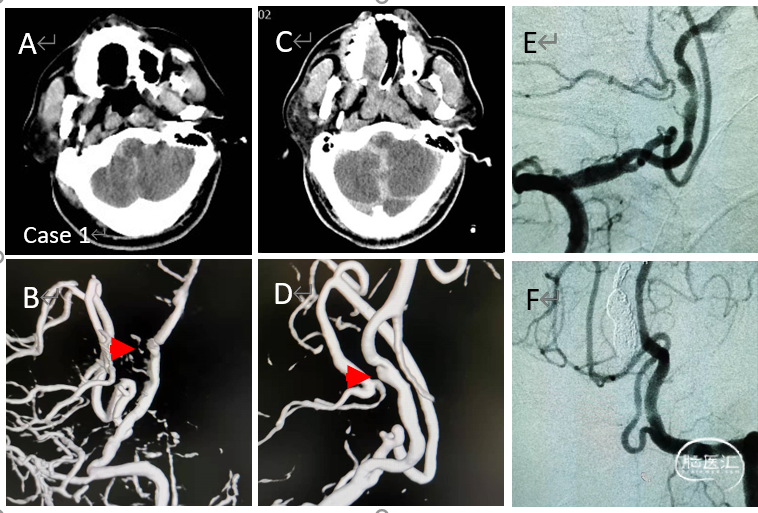

病例1

破裂的左侧椎动脉夹层动脉瘤

(Hunt-Hess 5级,致密栓塞)

病例2

破裂的大脑后后交通结合部多发动脉瘤

(Hunt-Hess 5级,致密栓塞)